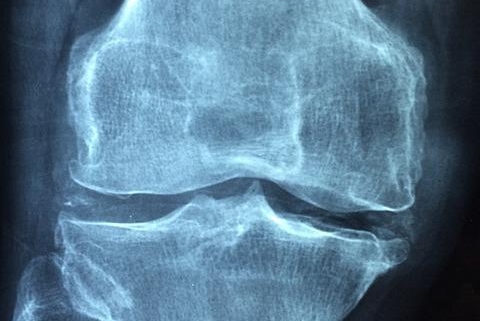

Imagine your joints like well-oiled hinges on a door. Cartilage acts as the smooth surface that allows the bones to glide over each other without friction. In OA, this cartilage wears down, causing the bones to rub together. This can lead to:

While OA can affect any joint, it most commonly occurs in the:

Knees: A leading cause of knee pain and disability